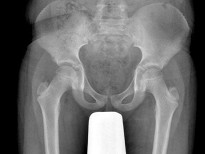

男,根据其正常骨盆影像图像,判断其最可能的年龄()

题型: 单选题 分类: 放射医学

• A.5岁左右

• B.10岁左右

• C.15左右

• D.20岁左右

• E.25岁左右